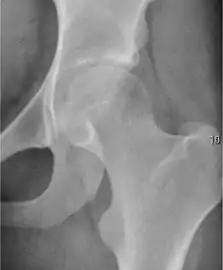

Plain radiography allows us to categorize the hip as normal or dysplastic or with impingement signs (pincer, cam, or a combination of both). Besides these, pathologic processes like osteoarthritis, inflammatory diseases, infection, or tumors can also be identified (Figure 1).[1]

Figure 1.

Radiography in normal hip

X-ray in pincer impingement type of hip dysplasia

X-ray of cam

Hip in osteoarthritis

Septic arthritis

- Osteoarthritis

In adults, one of the main indications for radiographs is the detection of osteoarthritic changes (Figure 1(e)). Nevertheless, radiographs usually detect advanced osteoarthritis that can be graded according to the Tönnis classifications. The grading system ranges from 0 to 3, where 0 shows no sign of osteoarthritis. Intermediate grade 1 shows mild sclerosis of the head and acetabulum, slight joint space narrowing, and marginal osteophyte lipping. Grade 2 presents with small cysts in the femoral head or acetabulum, moderate joint space narrowing, and moderate loss of sphericity of the femoral head. Grade 3 is the severest form of osteoarthritis, which manifests as severe narrowing of the joint space, large subchondral cyst with productive bone changes that may lead to deformity of the bone components of the joint, while secondary osteoarthritis due to calcium pyrophosphate deposition can be diagnosed when calcification of hyaline cartilage and fibrocartilage is detected.[1]

There are other pathological conditions that can affect the hip joint and radiographs help to make the appropriate diagnosis. Acute bacterial septic arthritis can be diagnosed by radiographs when a fast regional osteoporosis and destructive monoarticular process develops (Figure 1(f)). In case of tuberculous or brucella arthritis it is manifested as a slow progressive process, and diagnosis may be delayed.[1]